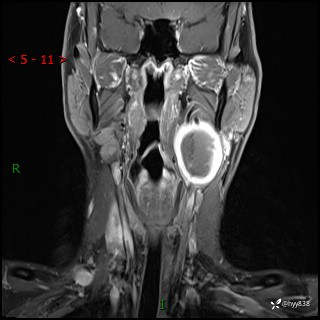

年轻小伙,发现左侧颈部肿物3年余,逐渐增大---结果公布~

现病史:患者约3年前因感冒发现左侧颈部长一肿物,约半个鸡蛋大小,无明显疼痛及其他不适,一直未行特殊处理。3个月前发现左侧颈部肿物变大,随后至当地市第二人民医院耳鼻喉科行左侧颈部彩超示:左侧颈部囊实混合性包块;喉部MPR示:左侧胸锁乳突肌内前方占位,累及左侧喉旁间隙,建议增强扫描。建议手术治疗。患者考虑。随后至我院肿瘤科就诊,行细胞学穿刺示:考虑血管源性肿瘤可能,建议进一步检查。建议至我院口腔科就诊,行颌面部MRI示:左侧颌下腺后方团状异常信号灶,建议增强。建议手术治疗。为求进一步治疗,门诊以“左侧颈部肿物”收入院。 起病以来,患者神志清、精神良好,饮食睡眠良好,大小便正常,体重未见明显变化。

颈部MRI平扫+增强